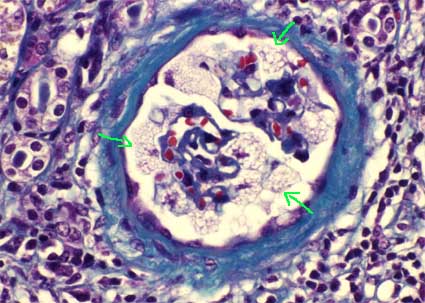

There is a slight increase in the matrix and mesangial cellularity that can be progressively increased. In silver-methenamine stains, thickening of the capillary walls and, in some cases, multilamination can be evidenced. The Bowman capsule appears with varying degrees of thickening. In more advanced stages there is global sclerosis of glomeruli and we can also see segmental sclerosis, sometimes with hyalinosis. In young men we can see small glomeruli with few capillaries giving an appearance called "fetal".

Figure 1. The alterations of the glomerular basement membrane in the Alport syndrome can not be evidenced clearly in the conventional histological study; In some cases we can see irregularities of the capillary wall (arrows), with areas of thick appearance, thinner areas and, in some cases, laminated aspect of it. (Methenamine-silver, X1,000))